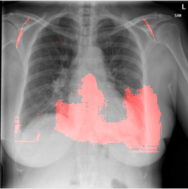

4.2.1 Cardiomegaly Localization

The localization of abnormalities in cardiomegaly examples are shown in Fig. 7. Here, of the image area is shown which has the highest sensitivity. It can be observed from the figures that the network is indeed most sensitive to the region where the heart is larger than a normal heart. We have performed this experiment on cardiomegaly and normal images and found this localization to be consistent for most examples. There is not much functional difference between a normal and cardiomegaly example other than the fact that the heart in cardiomegaly is larger than a normal heart. Given the fact that the normal images could also have various size of heart depending on the age or physical attributes of a patient, we found this level of localization sensitivity to be remarkable. Also interesting is the fact that the standard rule based features like CTR and CTAR take into account the relative size of heart and lung to determine if there is cardiomegaly present or not. In the DCN localization experiment, we see counter-intuitively that most of the signals contributing to the softmax score are coming from the heart only. This means that there are characteristic features in the shape of the heart and its surrounding regions that alone is sufficient to detect cardiomegaly. The lung and its relative size are probably less important features when trying to detect cardiomegaly. This observation is counterintuitive and needs to be explored further in future work.

8 Additional Examples of Localization

In this section we show more examples of localization. Few localization samples are shown in Fig. 11. It can be observed that, in the CXRs with Cardiomegaly (Fig. 11(a) and (b)) a fine localization around the heart is observed. In the normal CXRs (Fig. 11(c) and (d)) such localization is not observed. Rather the lowest probabilities are spread out in the CXR image. It is interesting to note that, the localization algorithm gets low probability where the heart is enlarged during cardiomegaly, but the proportion is small compared to the localization in other areas of normal CXRs. In order to observe the performance of the heat map we computed histograms of heat maps of each of the 100 CXRs in the test set for Cardiomegaly detection and average histograms are shown in Fig. 11(e) and (f) for CXRs with Cardiomegaly and normal CXRs, respectively. It is to be noted that, the histograms include both success and failure cases. It can be observed that, for CXRs with Cardiomegaly the classifier is highly sensitive toward Cardiomegaly detection even under occlusion. This indicates that, the classifier primarily looks for local features in a CXR instead of some feature that is spread out in the entire CXR. However, the classifier is not sensitive toward normal CXRs under occlusion. Rather, the probabilities are spread out in the probability spectrum. After that, we analyzed the failure cases where the classifier is unable to classify the image correctly. Two such examples of failure cases are shown in Fig. 12. The localized CXR shown in Fig. 12(a) contains Cardiomegaly whereas the classifier detects it as normal. However, the localization shows that it localizes around heart quite well despite the in accurate classification. On the other hand, Fig. 12(b) shows an example of normal image which has been classified as Cardiomegaly by the classifier. There is stronger localization around the hear that that is observed for normal images as in Fig. 11(c) and (d), however, like those images the localization is spread out.